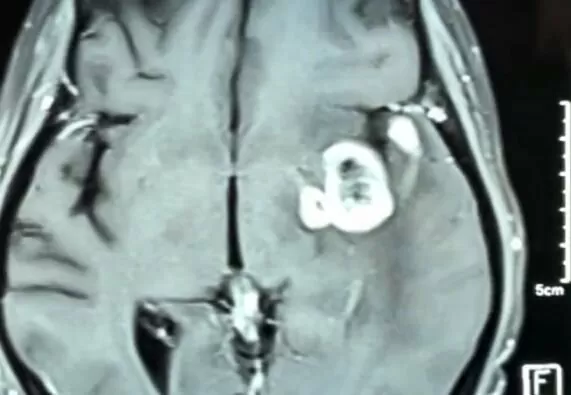

В діагностиці гліом головного мозку основними методами є МРТ головного мозку із контрастуванням, КТ / спіральна КТ.